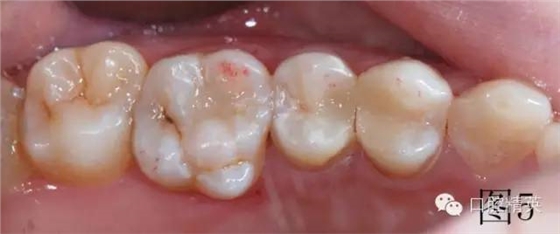

調(diào)牙合,圖5中上頜第一磨牙近中頰尖有紅色咬合點,此為牙合干擾點,調(diào)磨至沒有,最后拋光。治療結(jié)束,邊緣非常密合,患者非常滿意,沒有感到橡皮障任何不舒服的地方,唾液可自行吞咽。